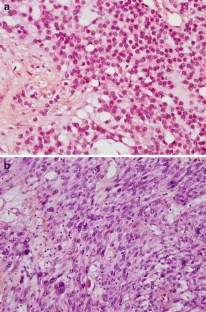

Microcystic stromal tumors (MCST), first described in 2009 by Irving et al., are rare ovarian neoplasms. The entity was introduced into the 2014 WHO classification of tumors of female reproductive organs in the group of sex cord-stromal tumors, which is rather heterogeneous. We studied three cases of ovarian tumor with the characteristic morphological features and immunohistochemical marker profiles of MCST. The three tumors showed micro, and macrocystic patterns with solid areas, and were composed of small round to spindle-shaped cells, without atypia. The tumors diffusely and strongly expressed CD10, FOXL2, and nuclear β-catenin, but without immmunoreactivity for hormone receptors, calretinin, or inhibin. Genome analyses showed no somatic mutation of exon 1 of the FOXL2 gene and of exons 24 and 25 of DICER1 gene, the latter not having been reported previously. The patients are well, without evidence of tumor progression 1 to 10 years after diagnosis.

Fig. 2